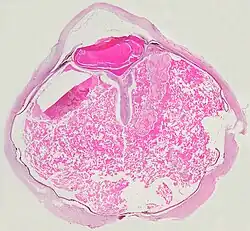

A case of Coats' disease, showing total exudative retinal detachment, and subretinal exudate containing cholesterol crystals (H&E)

Microscopically, the wall of retinal vessels may be thickened in some cases, while in other cases the wall may be thinned with irregular dilatation of the lumen.[11] The subretinal exudate consists of cholesterol crystals, macrophages laden with cholesterol and pigment, erythrocytes, and hemosiderin.[12] A granulomatous reaction, induced by the exudate, may be seen with the retina.[13] Portions of the retina may develop gliosis as a response to injury.